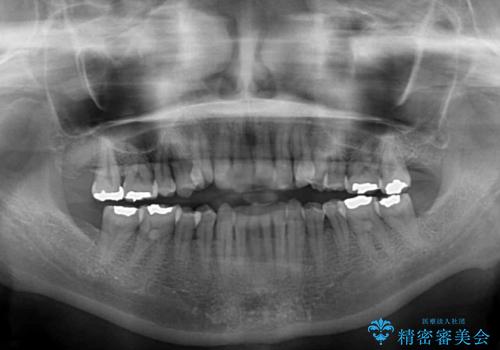

- 歯列不正と、どこで咬んで良いのか分からない咬み合わせを気にして来院された患者様です。

下顎骨は左側にシフトしており、咬み合ったときには奥歯と前歯の一部しか接触していない状態でした。

骨格的な左右差は歯列矯正は改善できないため、上下歯列が全体的に接触することをゴールとしてインビザラインにて矯正治療を行うこととしました。